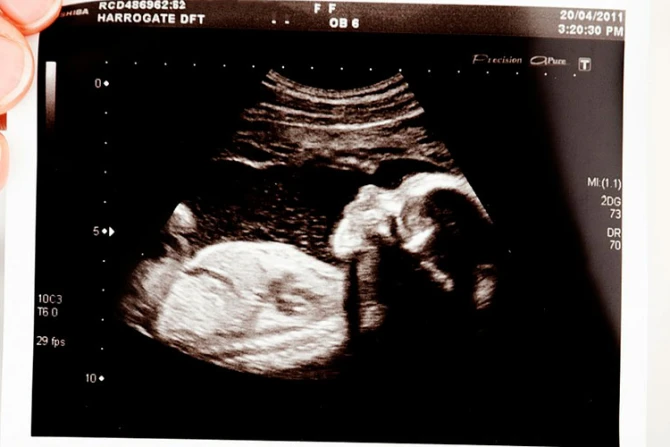

"Las mujeres embarazadas tendrán la oportunidad de ver a su propio bebé y escuchar los latidos del corazón", declaró Pro-Life Utah.

Además, resaltó que las estadísticas muestran que "hasta el 80% de las mujeres que desean realizarse un aborto experimentan un cambio de opinión y eligen quedarse con su bebé al ver el ultrasonido".

"La mentira del 'grupo de células' está expuesta, y las mujeres que ven su ultrasonido pueden darse cuenta de que es un bebé", agregó.